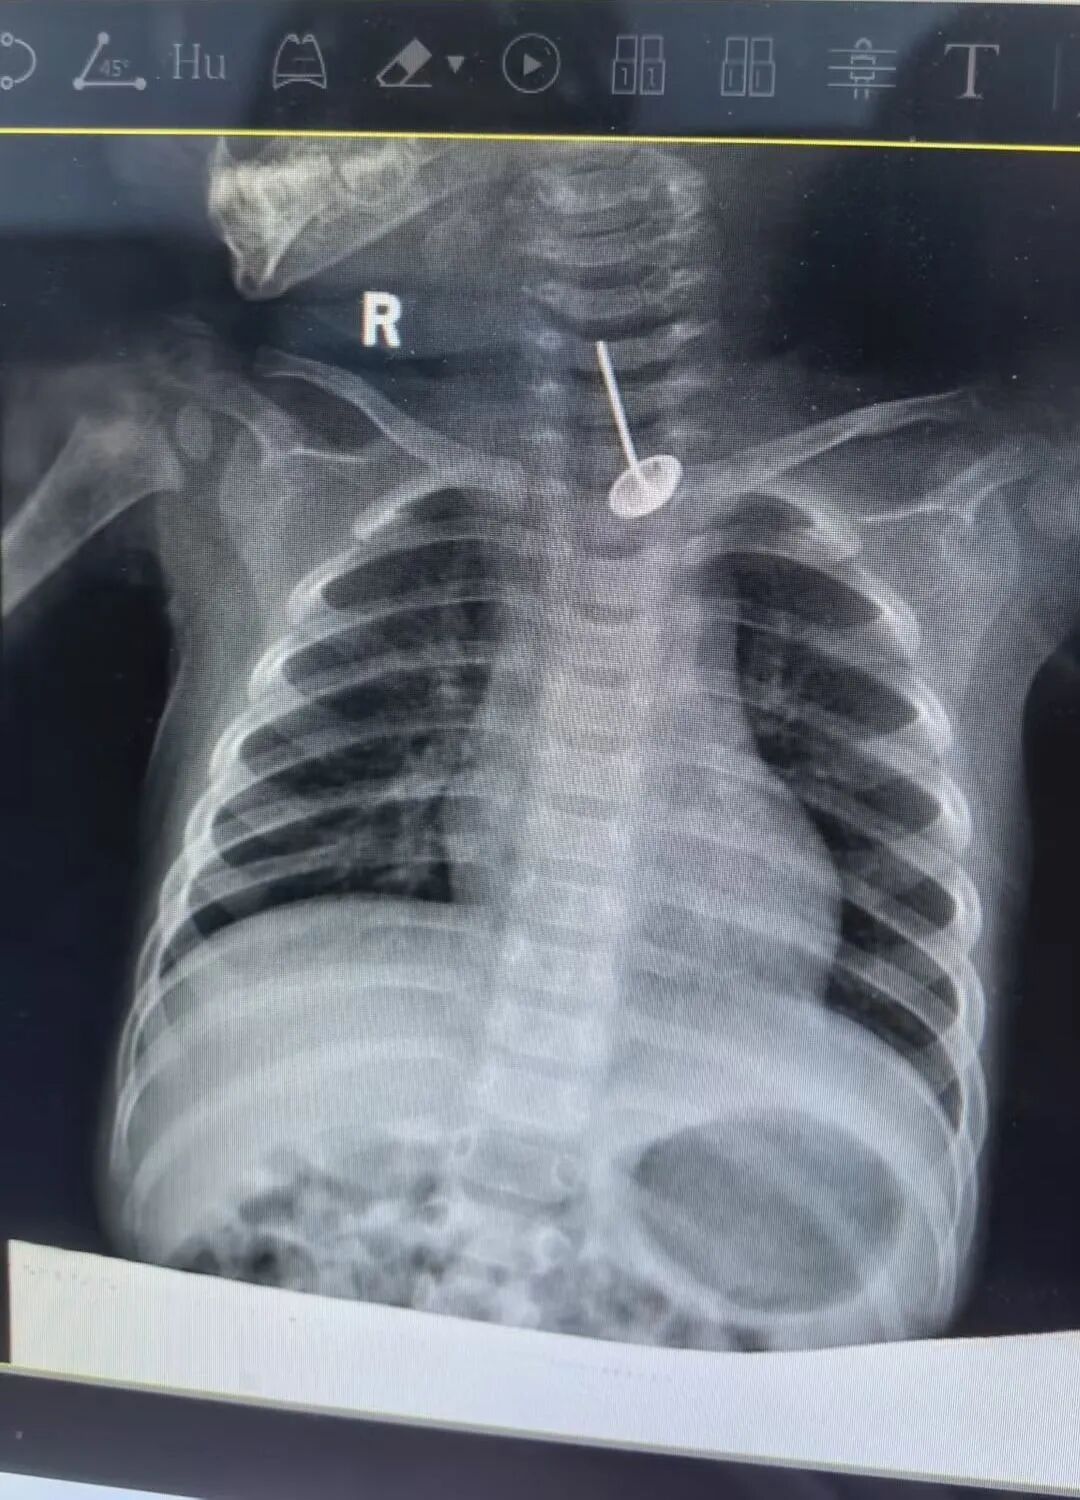

入院后,医生准备为小西实施全麻下口腔内裂伤清创缝合术。然而,就在术前完善胸片检查时,医护人员发现了更加惊险的一幕:小西食管内竟卡着一个图钉样的尖锐金属异物!胸部增强CT检查显示,该异物长达3厘米,已刺破食管壁,尖端紧邻主动脉弓,一旦刺穿大血管,瞬间便会引发大出血,生命危在旦夕。